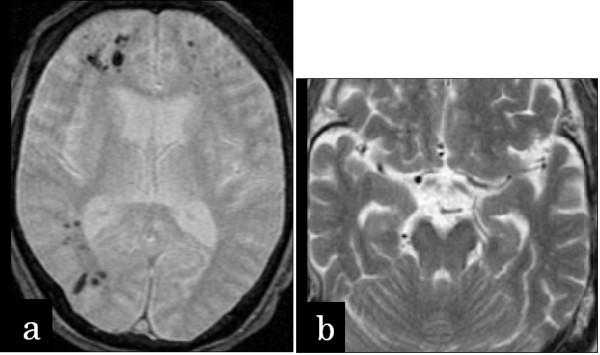

This is the first report of a case of cerebral air embolism as a result of spontaneous perforation of an ulcer in the constructed gastric tube into the pulmonary vein during post-operative follow-up in a patient with esophageal cancer.

这是首例报告一例因构建的胃管中的溃疡自发性穿孔进入肺静脉而导致的脑空气栓塞的病例,该病例发生在食管癌术后随访期间。

穿透性胃溃疡导致脑空气栓塞是一种罕见的并发症,但对于有胃管食管切除术病史且出现急性神经症状的患者,应考虑这种并发症。